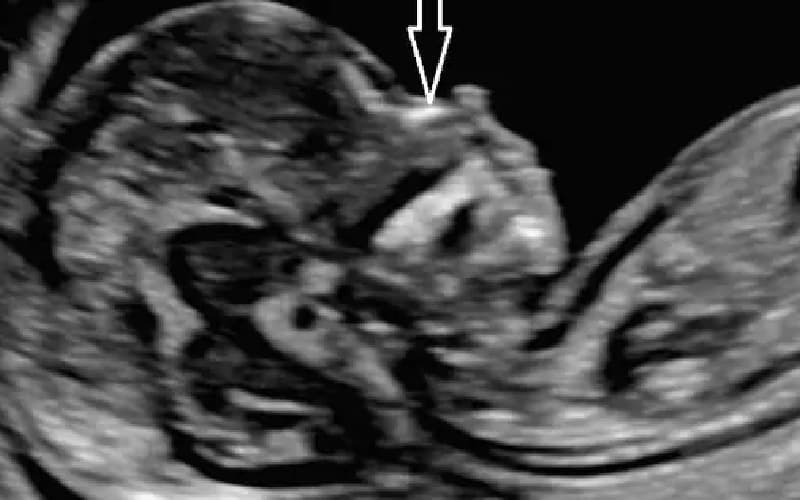

Thông thường, xương mũi bắt đầu được quan sát từ tuần thứ 12 của thai kỳ. Tuy nhiên, từ tuần 19 đến 22, cấu trúc này mới phát triển rõ rệt để có thể đo lường chính xác hơn.

Riêng với mốc chiều dài xương mũi thai nhi 22 tuần, chỉ số khoảng 5,7 mm được xem là đạt chuẩn bình thường (bách phân vị thứ 50).

Đây là nỗi lo lắng chung của nhiều phụ huynh khi nhận kết quả siêu âm. Tuy nhiên, theo chuyên gia, tình trạng xương mũi ngắn chỉ được xem là dấu chứng yếu của hội chứng Down khi chỉ số này dưới 3 mm ở tuần thai 21-22.

Lời khuyên từ chuyên gia: Việc đo chiều dài xương mũi có độ chính xác khoảng 95,5% nhưng phụ thuộc nhiều vào thiết kế máy siêu âm và tay nghề bác sĩ. Nếu xương mũi bé ngắn, bác sĩ có thể chỉ định theo dõi thêm sau 2 tuần hoặc thực hiện chọc ối nếu có các dấu hiệu nguy cơ cao khác đi kèm.